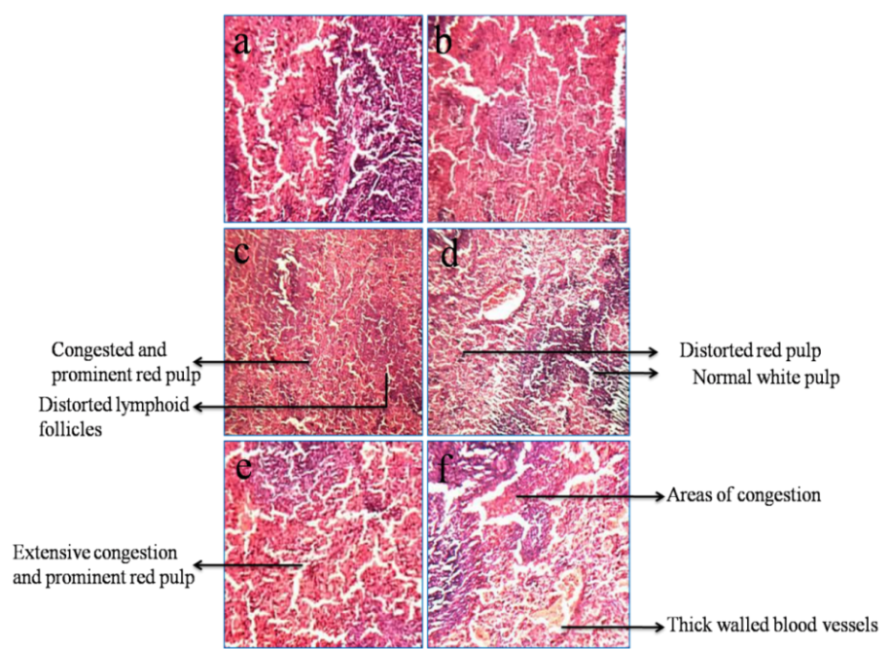

Spleen

The spleen sections of rats treated with various concentrations of CFA-NPs showed severe damage of tissues in all the treated concentrations when compared to control groups as shown in fig. 3. Both the control sections show normal spleen. At lower concentration (500 mg/kg bw of CFA-NPs) the spleen section showed congested and prominent red pulp and distorted lymphoid follicles.

Fig. 3: Spleen sections of rats dermally treated with various concentrations of CFA-NPs for 14 days (a-normal control, b-vehicle control, c-500 mg/kg bw of CFA-NPs, d-1000 mg/kg bw of CFA-NPs, e-1500 mg/kg bw of CFA-NPs and f-2000 mg/kg bw of CFA-NPs)

The rats treated with 1000 mg/kg bw of CFA-NPs showed congested spleen with distorted red pulp and normal white pulp. At 1500 mg/kg bw of CFA-NPs treated spleen section showed extensive congestion and prominent red pulp. At higher dose 2000 mg/kg bw of CFA-NPs treated group showed spleen with areas of congestion and thick walled blood vessels. The histopathology of spleen tissues showed very severe damage in all treated concentration of CFA-NPs. In all sections there was appearance of red pulp; this was not found in the control groups. In all treated concentrations of CFA-NPs there were notable changes found in the tissues when compared to the control.